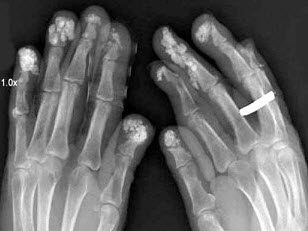

57、多项选择题 痛风的X线表现有()

A.早期为关节周围软组织肿胀

B.骨皮质出现硬化或多处波浪状凹陷

C.关节周围软组织出现结节状钙化影

D.骨性关节面不规则或穿凿状破坏

E.关节间隙变窄,甚至纤维性或骨性强直